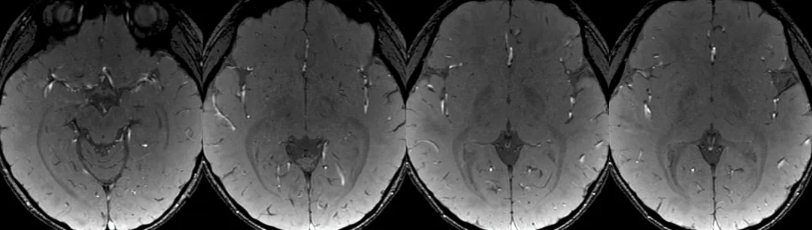

是不是静脉畸形, 整一个磁敏感成像SWAN:2/-1mm

SWAN进行厚层(6mm)最小信号强度投影重建(MinP)效果, 一根正常的小静脉在此区域走行,其余未见显著异常。